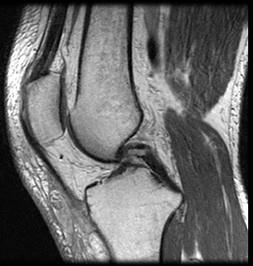

问题 男,39岁,右膝关节有外伤史,感膝关节疼痛,活动后加剧,请结合所提供的图像,选择最佳选项 ( )

选项 A、胫骨骨折 B、后十字韧带撕裂 C、前十字韧带撕裂 D、内侧半月板撕裂 E、未见异常

答案 B